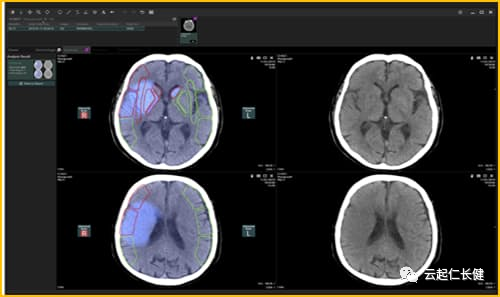

对于脑卒中患者的CT图像,佳能医疗系统公司开发的AI能突出显示其中应注意的地方

佳能的医疗器械子公司“佳能医疗系统公司(Canon Medical Systems)”在CT、MRI上安装了能让图像更加高清的AI。这将大大有助于CT的低剂量拍摄,并且还能缩短MRI的成像时间。

2020年7月,这款通过AI对CT拍摄的脑卒中患者图像进行分析的软件正式上市。它的强项是分析出血状态和血流状态,大大节省了医生确定治疗方案的时间。有助于提高急救现场的效率。